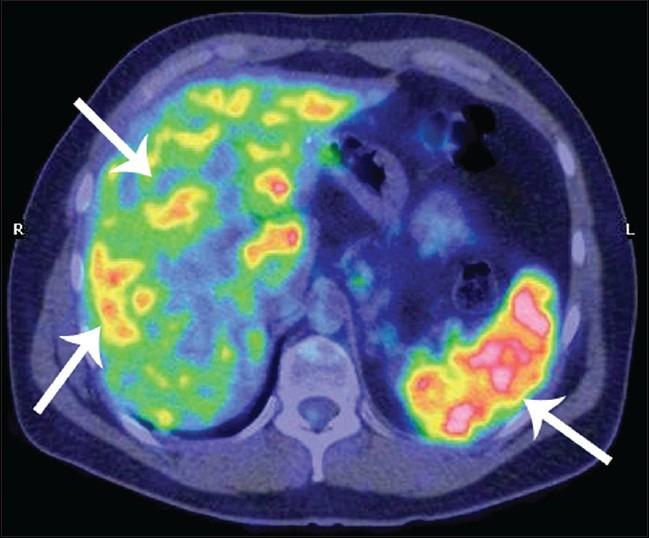

Positron emission tomography (PET) in combination with computed tomography (PET-CT) is commonly used to identify malignant lesion in the lung. Despite there being only a few reports in literature, PET-CT imaging may have many advantages in the study of sarcoidosis, being useful in the diagnosis as well as in monitoring the response to treatment. The object of this case report is to highlight the clinical utility of integrated PET-CT imaging for evaluation of patients with systemic sarcoidosis and for comparing baseline findings to follow-up readings.

正电子发射断层扫描(PET)与计算机断层扫描(PET-CT)相结合常用于识别肺部恶性病变。尽管文献中仅有少数报道,但PET-CT成像在结节病研究中可能具有许多优势,对诊断以及监测治疗反应均有用。本病例报告的目的是强调PET-CT成像在评估系统性结节病患者以及比较基线检查结果与随访读数方面的临床应用价值。